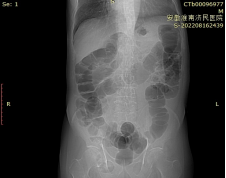

定位像

俯卧超薄断层像